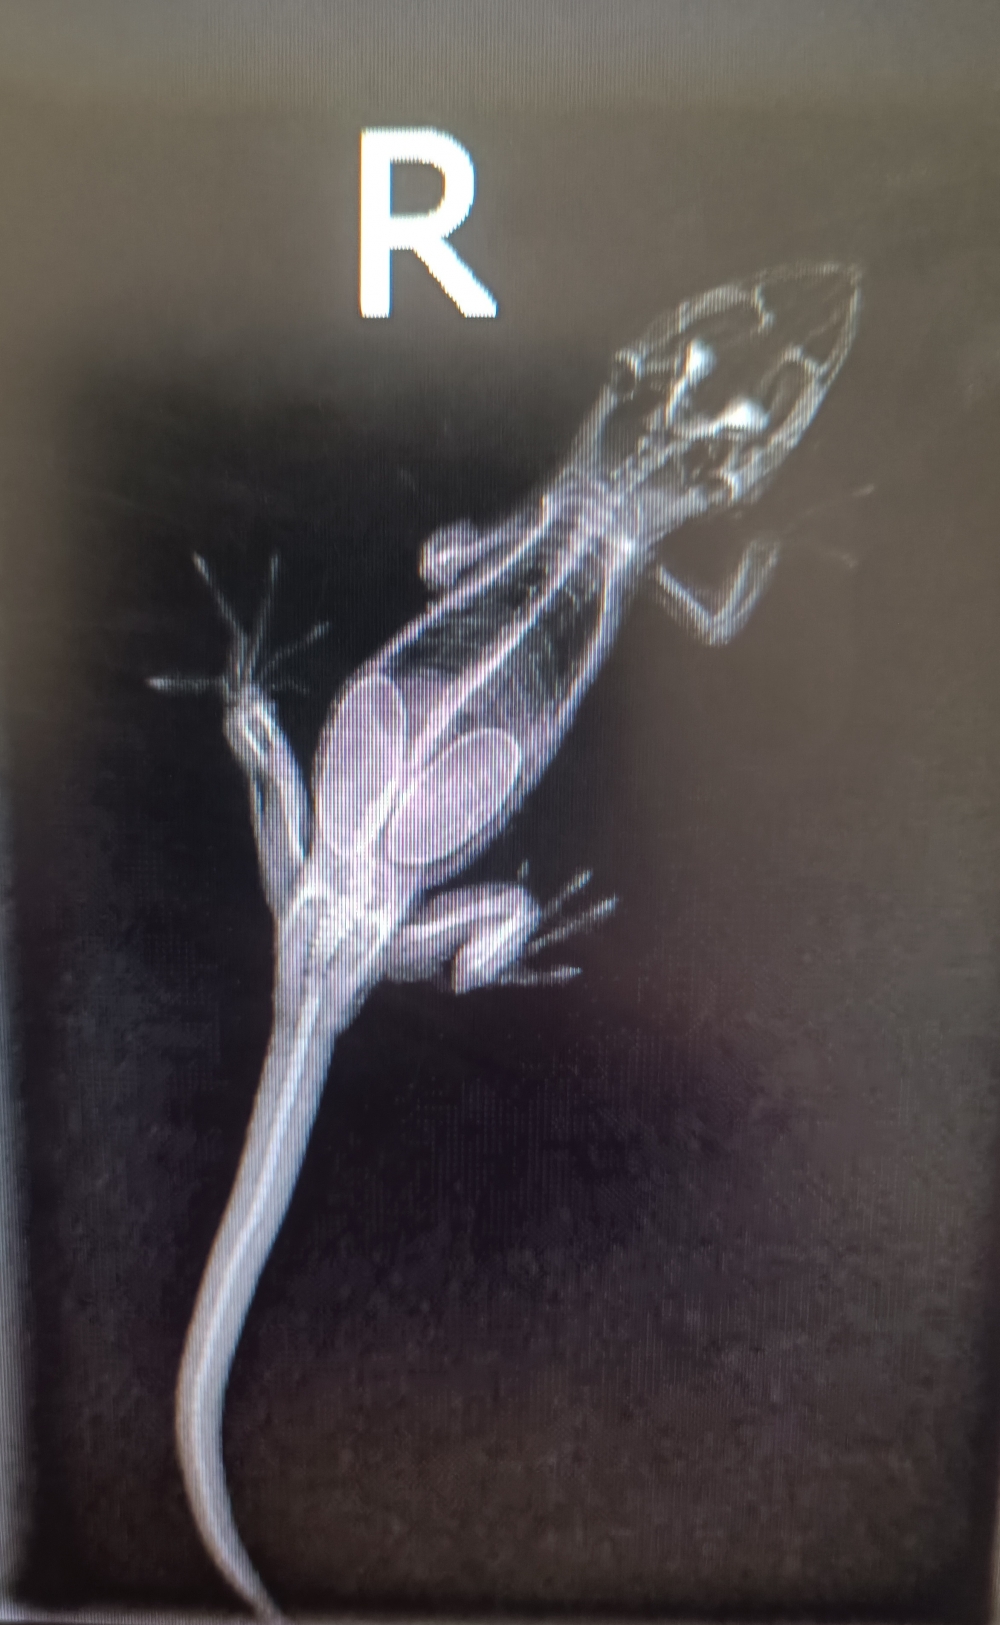

A práve tento druh zavítal nedávno na našu kliniku. Majitelia už dlhšie pozorujú v truse pagekónov makroskopicky parazity. Ich správanie sa výrazne zmenilo - boli menej aktívne, podráždené a agresívne voči sebe aj majiteľom. Ďalším problémom bola inapetencia. V rámci vyšetrenia pacienti absolvovali základné klinické vyšetrenie s dôslednou anamnézou. Trus bol mikroskopicky vyšetrený na našom pracovisku aj odoslaný do laboratória pre vylúčenie prítomnosti vajíčok. Po aplikácii potrebných antiparazitík sa pacientom výrazne polepšilo, apetít sa navrátil, agresivita vymizla a navrátila sa aj pôvodná aktivita. Netreba však zabúdať na to, že samotná terapia nestačí a v prípade výskytu parazitov v teráriu je potrebná aj dôkladná dezinfekcia prostredia, aby sa zabránilo reinfekcii.